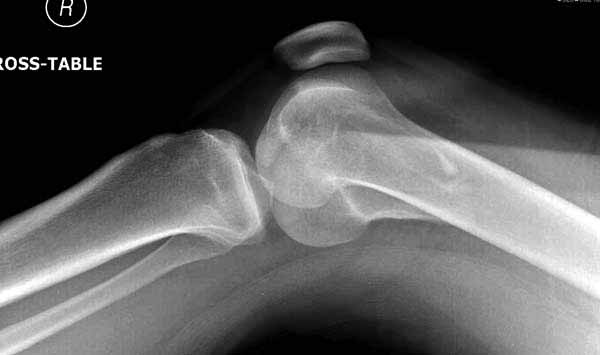

>Сразу не обратил ваше внимание именно на это, что сломаны оба мыщелка, и больший является именно медиальным мыщелком

По снимку вроде одиночный простой мыщелковый перелом, и такой внутрисуставной перелом не обязательно дистрагировать на скелетном вытяжении, потому что не не нарушается непрерывность колонны с одной стороны. И для таких простых переломов подойдет любой метод: 95 градусная пластина, Lat. Condylar Butress пластина или ретроградный гвоздь. А для особых энтузиастов которые желают антеградную фиксацию, возможно легко найти трохантер у алкоголиков или дистрофиков. А вот у откормленных Макдональдскими гамбургерами? Если поискать у них тоже можно найти, но стоит ли?

У больных как в этом случае, с вовлечением двух мыщелков правильно, что сделали вытяжение до операции. Здесь имеется флексионный компонент на другой стороне, и я бы рекомендовал операцию делать из двух доступов. Сперва фиксировать медиальную колонну custom made пластиной, обычно 1/3 тубулярной пластиной в 4.5 мм, потому что пока производители опаздывают с медиальной пластиной.